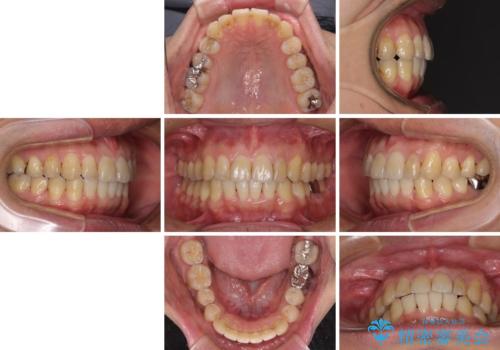

- 前歯のデコボコや八重歯を気にして来院された患者様です。

インビザラインを用いて、歯列を整えることとしました。

下顎前歯は後戻りを起こしやすいため、舌側を細いワイヤーで固定し、マウスピース型リテーナーで保定を行うこととしました。